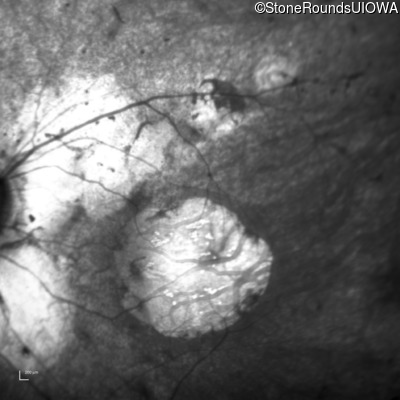

Age at visit: 15 years

This 15 year old male had a macular abnormality noted two weeks ago when he was refracted for his first pair of glasses. Bone spicule-like pigmentation was first noticed a year later (age 16) during a routine follow-up eye exam.